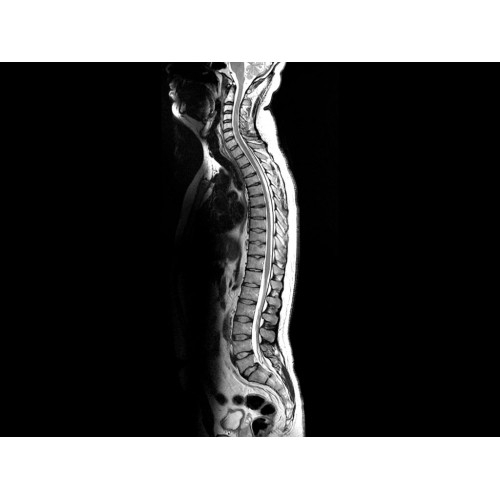

• Визуализация всего позвоночника слиянием двух участков — получить изображение всего позвоночника можно намного быстрее.